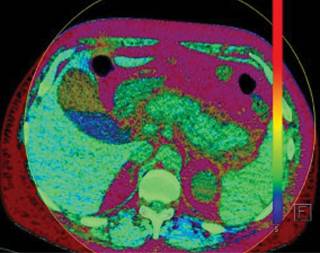

Masculino de 32 años de edad, sin antecedentes personales patológicos de importancia, acude al servicio de urgencias por presentar dolor abdominal transfictivo a nivel de epigastrio, acompañado de vómito de contenido alimenticio en dos ocasiones. Se solicitó estudio de tomografía abdominal por médico tratante, la cual se realizó con modalidad de energía dual, y definió múltiples imágenes redondeadas en vesícula biliar en relación a litiasis (Figura 1) así como aumento del volumen pancreático y estriación de la grasa adyacente compatible con pancreatitis Balthazar D (Figura 2).

Figura 1: Corte axial de tomografía computarizada de abdomen de energía dual, donde se hacen evidentes diferentes contrastes en vesícula biliar, y se define la morfología de múltiples litos vesiculares (azul).